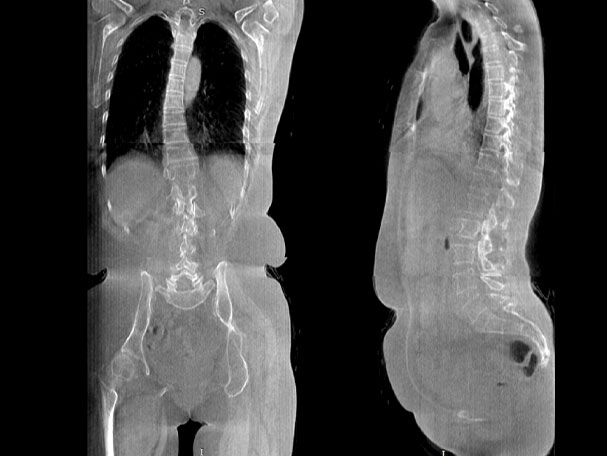

腰椎

VR体绘制重建

气道三维影像重建